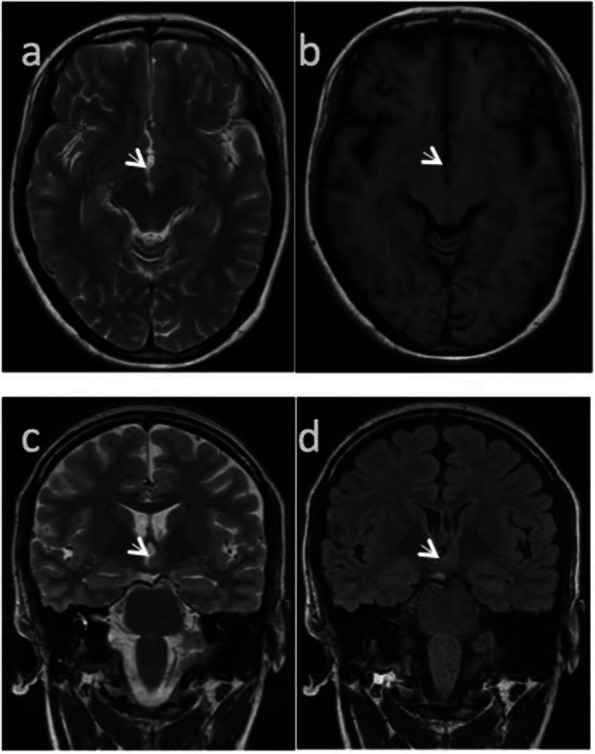

Background: Hypothalamic hamartoma (HH) is a congenital non-progressive lesion of hypothalamus during fetal development. Mass-like lesions in different anatomical locations often develop a variously disabling course presenting with cognitive decline, psychiatric symptoms, as well as multiple seizure types. As a rare disease, HH is relatively common in infants and children, but it is extremely rare in adults.

Case presentation: We reported a case of adult-onset hypothalamic hamartoma, and summarized and analyzed relevant reports and studies of HH worldwide. The patient had clinical manifestations characterized by multiple seizure forms. After stereotactic radiofrequency thermocoagulation and drug treatment, the condition was effectively controlled. The patient was followed up till October 2022, with no recurrence of seizures.

Conclusions: Epilepsy caused by HH can resemble that of temporal lobe seizures, as HH forms a complex epileptogenic network with other regions of the brain through anatomical and functional connections. Early treatment of HH can provide better control of the symptoms of epilepsy, and patients with longer disease courses may have more complications.